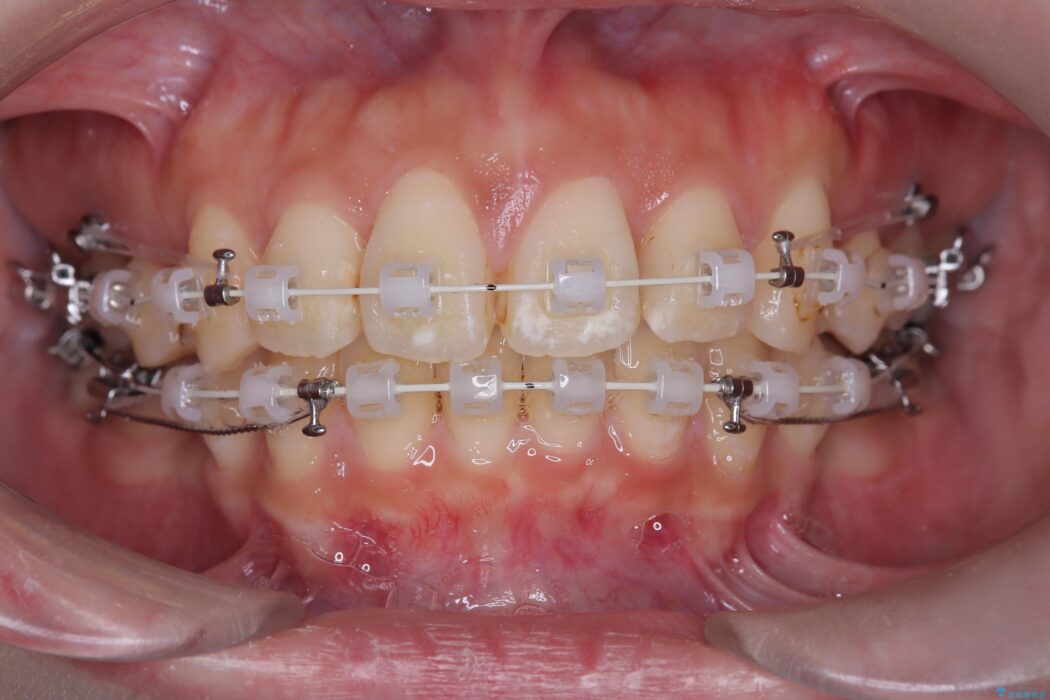

確実な歯の移動を実現するため、ワイヤー矯正装置を使用しました。

口元の突出感が解消し、Eラインが劇的に改善しました。機能的な噛み合わせと美しい審美性を両立し、理想の口元を獲得していただけました。